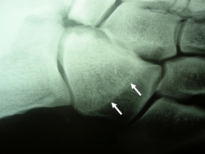

Exemple de fracture de fatigue du 3e métatarsien gauche:

fissure visible sur le cliché 3/4 |

apparition d'un cal en "olive" |

A partir de la 3e semaine apparaissent les signes de consolidation osseuse sous la forme d’un cal formé par la transformation osseuse de l’hématome survenant autour de la zone fracturée.

Ce cal peut prendre la forme d’une « olive » se densifiant progressivement ou sous la forme de lamelles engainant l’os atteint (appositions périostées).